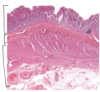

Esophagus – mucosa, submucosa, muscularis externa

Esophagus – mucosa – stratified squamous non-keratinized ep, lamina propria with small blood vessels, muscularis mucosa (smooth muscle)

Esophagus - submucosa (DICT) with blood vessels